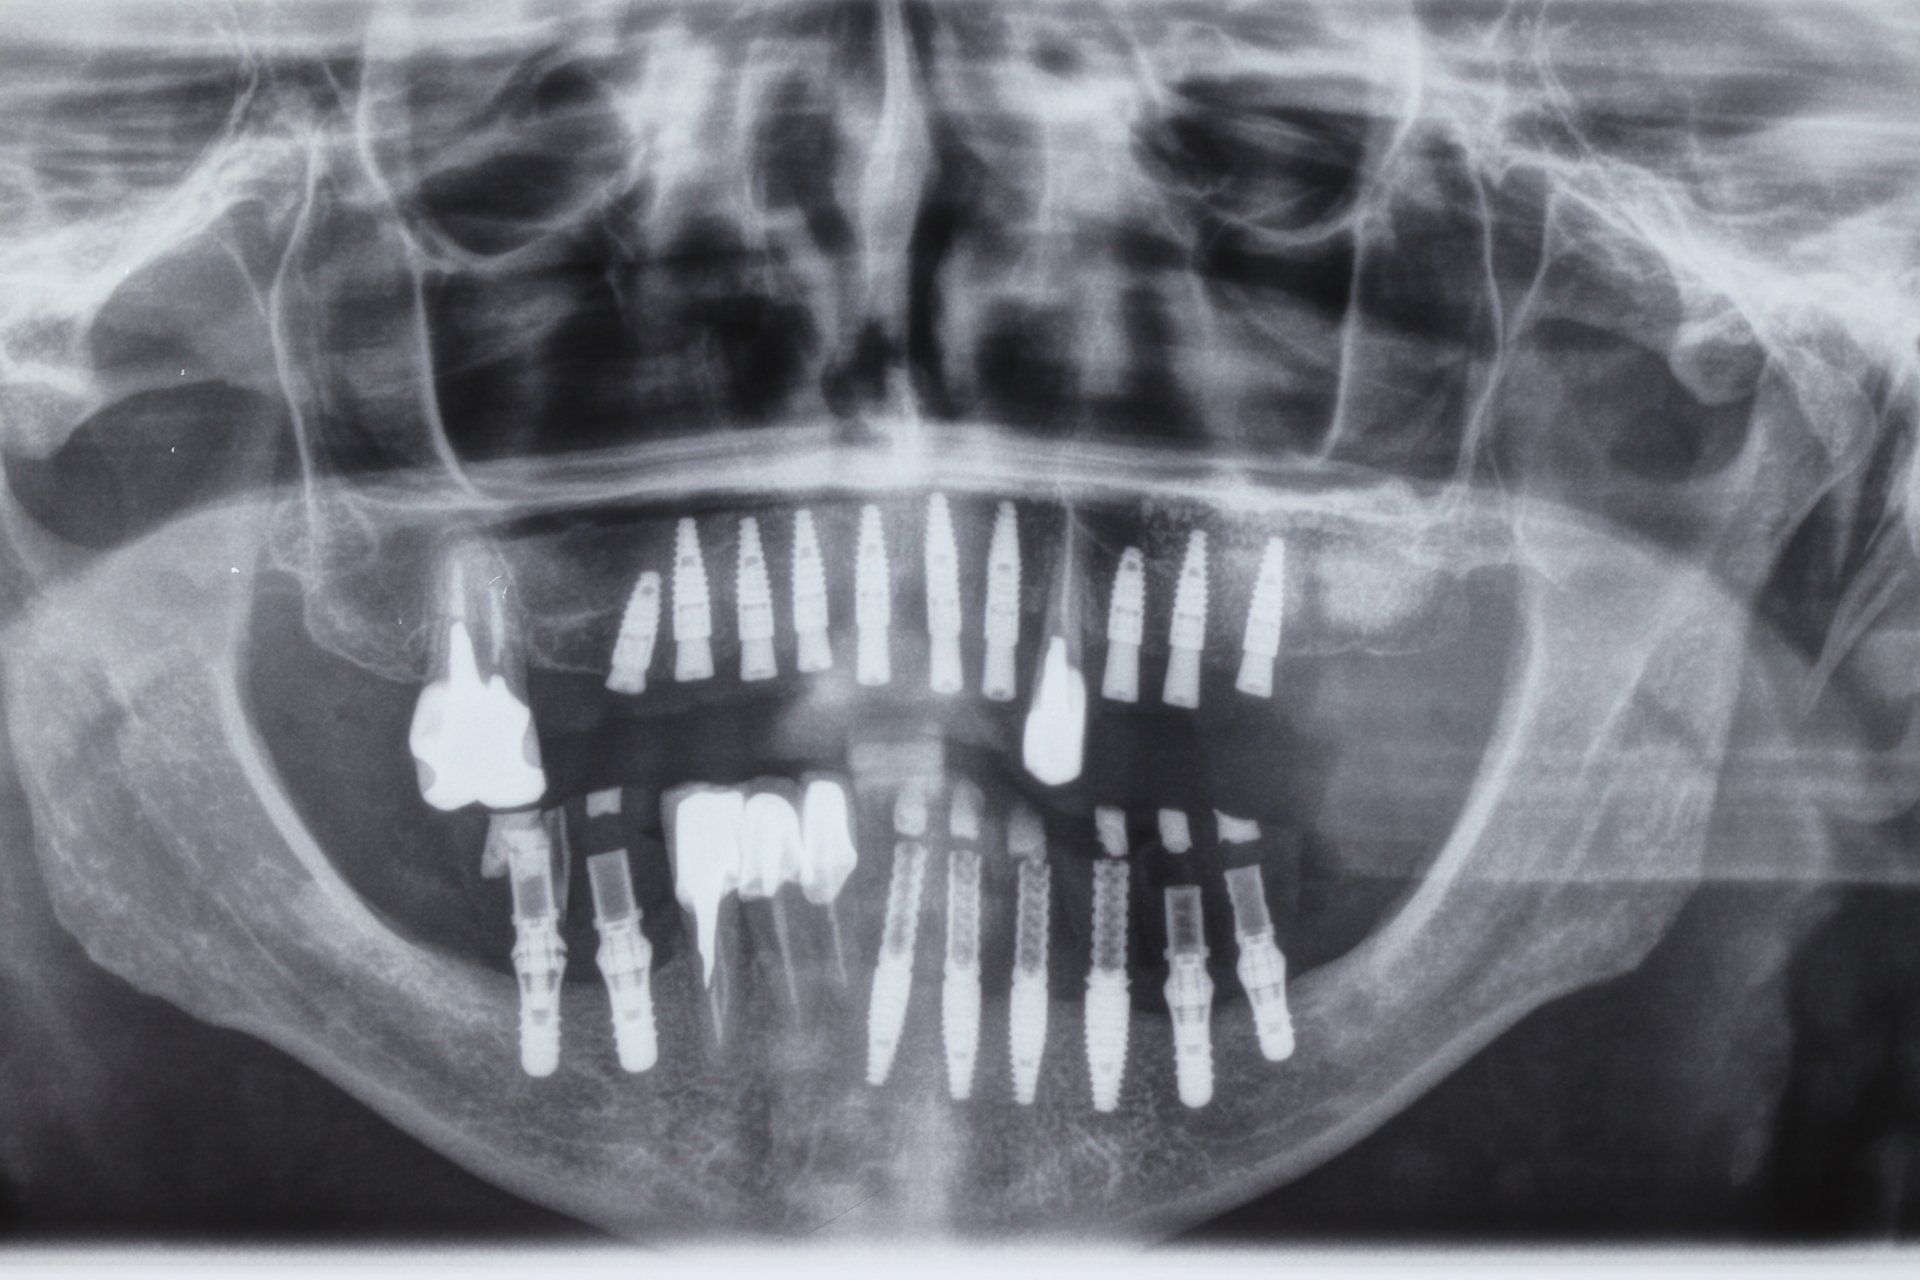

O Implante Dental é um tratamento de Odontologia para reposição dos dentes irrecuperáveis por meio de cirurgias e tratamentos ósseo integráveis.

As imagens apresentadas são apenas ilustrativas do que pode ser conseguido com alguns tratamentos odontológicos, não demonstrando garantia de resultados. Cada situação particular exige diagnóstico e planejamento adequados e individualizados.